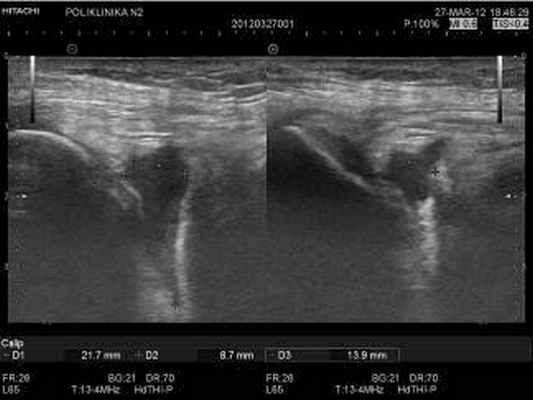

Изменения толщины синовиальной оболочки воспалительного генеза были подтверждены наличием выпота в полости сустава (Рис. 1, 2), как основного маркера воспаления сустава и усилением васкуляризации в режиме ЦДК и ЭК по сравнению с контрлатеральным одноименным суставом.

Рисунок. 1. Коленный сустав. Косая проекция выше надколенника по передней поверхности латерального мыщелка бедра Воспалительный выпот в небольшом объеме в полости сустава.

Рисунок. 2. Центральная часть полости коленного сустава. Косая проекция выше надколенника. Выпот в полости сустава однородной структуры в небольшом объеме в двух взаимно-перпендикулярных проекциях. Умеренно выраженное утолщение синовиальной оболочки, выстилающей полость сустава.

Толщина синовиальной оболочки изучалась на всем доступном для визуализации протяжении в различных отделах коленного сустава и ее измерения проводились в трех стандартных отделах. У каждого исследуемого пациента проводились измерения толщины синовиальной оболочки в определенных местах: в супрапателлярной сумке, в центральной части полости коленного сустава и в латеральном подсвязочном пространстве коленного сустава.

Частота локализации выпота в различных отделах коленного сустава и околосуставных сумках изолированно или в различных комбинациях изучалась на примере второй группы пациентов, состоящей из 308 пациентов с воспалительными заболеваниями коленного сустава. Данная группа состояла из 167 женщин и 141 мужчин в возрастной категории от 28 лет до 72 лет. Вычисления объема выпота проводились путем измерения трех сторон выпота в двух взаимноперпендикулярных плоскостях сканирования с применением функции « volume ».

В таблице 1 представлены результаты измерений толщины синовиальной оболочки в различных отделах коленного сустава 108 пациентов с длительностью течения воспалительного процесса в суставе не более 1,5 месяца. Градация толщины синовиальной оболочки в таблице составлена на основе трех степеней воспалительного процесса: незначительного, умеренного и выраженного. Воспалительные изменения синовиальной оболочки выражались в виде отклонений от нормативных значений в сторону увеличения толщины синовиальной оболочки. В результате полученных данных выявлено, что при воспалительном процессе коленного сустава степень изменений толщины синовиальной оболочки не равномерна в различных отделах одного и того же коленного сустава. Из таблицы видно, что максимальные значения толщины синовиальной оболочки определяются в супрапателлярной сумке (рис. 5). Меньшие значения толщины синовиальной оболочки определяются в латеральном подсвязочном пространстве коленного сустава (рис. 3,4). В центральной части полости коленного сустава изменения толщины синовиальной оболочки значительно менее выражены по сравнению с двумя предыдущими отделами (рис. 2). При различных степенях выраженности воспалительного процесса, основанной на клинических проявлениях, неравномерность изменений толщины синовиальной оболочки в различных отделах коленного сустава сохраняется c различной степенью выраженности изменений синовиальной оболочки. В данном случае выраженность воспалительного процесса в суставе влияет на степень изменения толщины синовиальной оболочки в различных отделах сустава. Например, при незначительном воспалительном процессе в коленном суставе толщина синовиальной оболочки, выстилающей полость супрапателлярной сумки, изменяется до 4 мм , синовиальная оболочка латерального подсвязочного пространства реагирует незначительно, а синовиальная оболочка центральной части сустава может иметь нормативные значения. При выраженном воспалительном процессе прослеживается та же последовательность выраженности изменений толщины синовиальной оболочки в изучаемых отделах. При выраженном воспалительном процессе толщина синовиальной оболочки супрапателлярной сумки более 6 мм , толщина синовиальной оболочки латерального подсвязочного пространства от 4 мм до 6 мм , толщина синовиальной оболочки центральной части сустава до 4 мм . Это доказывает неравномерность изменений толщины синовиальной оболочки в различных отделах сустава при различной степени выраженности воспалительного процесса. При ультразвуковом определении степени выраженности воспалительного процесса в суставе, основанном на изменениях синовиальной оболочки , нужно учитывать изменения синовиальной оболочки во всех отделах коленного сустава.